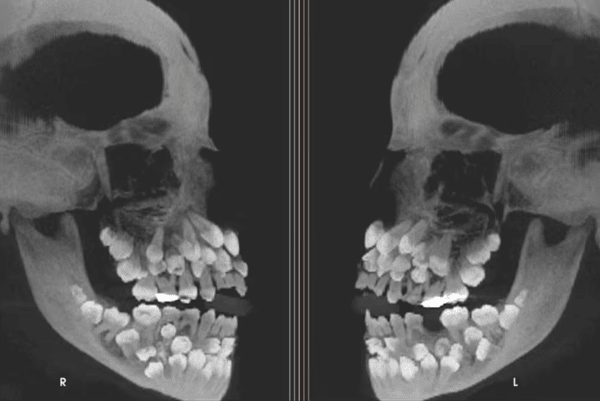

브라질의 한 소녀가 단순 유치 발치를 위해 병원을 찾았다가 전 세계적으로 유례없는 희귀 사례의 주인공이 됐다. 구강 내 치아 개수가 80개를 넘긴 사례는 극히 드물며, 이번 발견은 단순한 치과 이슈를 넘어 유전학과 발달의학까지 파장을 불러일으키고 있다. 11세 소녀의 엑스레이에는 유치 18개, 영구치 32개, 여기에 과잉치 31개까지 확인되면서 총 81개의 치아가 존재하는 것으로 나타났다. 일반적인 성인 치아 수가 32개라는 점을 감안하면 2.5배에 달하는 수치다.

이번 사례는 ‘다발성 과잉치증(multiple hyperdontia)’이라는 치과적 이상 현상으로 분류된다. 일반적으로 과잉치는 1~2개 정도가 드물지 않게 발견되지만, 10개를 넘는 경우는 희귀 질환 수준으로 여겨진다. 30개 이상의 과잉치가 동반된 경우는 전 세계적으로도 학계 보고가 손에 꼽힐 만큼 드물다. 문제는 과잉치가 단순히 숫자의 문제가 아니라 기능적, 구조적, 심미적 영향을 모두 유발할 수 있다는 점이다. 정상적인 치열 배열을 방해할 뿐만 아니라, 주변 치아의 뿌리를 압박하거나 턱뼈의 성장에 간섭할 위험도 존재한다.

이처럼 비정상적인 수의 치아를 가진 경우 단순 발치나 교정만으로는 해결이 어렵다. 특히 잇몸 깊은 층에 묻혀 있는 과잉치는 치아 형태가 정상이거나 뼈 속에 포함돼 있어 외형만으로는 구분이 힘들다. 무분별한 제거는 턱뼈 손상이나 신경 자극을 유발할 수 있기 때문에, 정밀한 영상진단과 협진 시스템이 핵심이다.